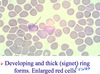

P. vivax

- Epidemiology

- Host

- Vector: anopheles mosquito

- Features: hypnozites in liver (sleeping/resting zoites causing relapse of disease, need to treat this)

- developing and thick (signet) ring forms

- enlarged RBC

- Sx: fever every 48 h

- Dx: chloroquine + primaquine (hypnozoites)

- Rx

- Control